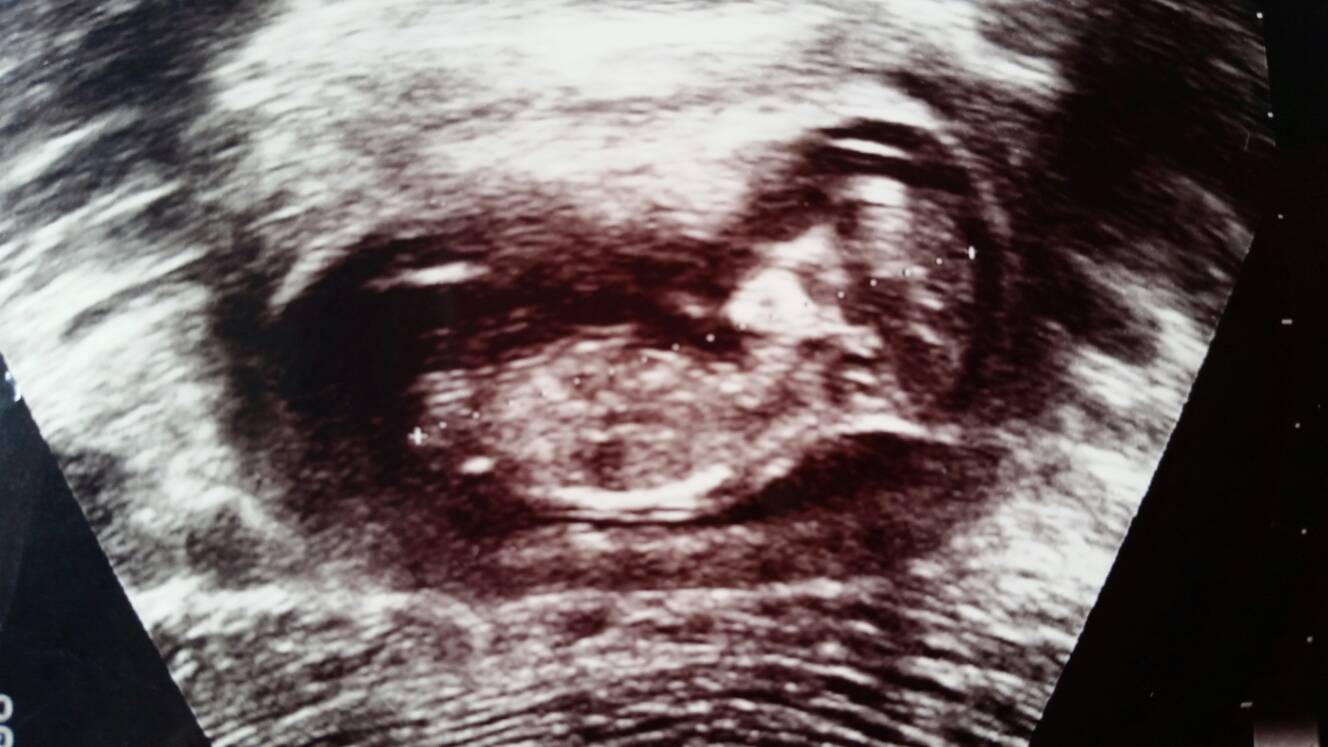

Girl

Hoe far in the 12 WK's? It looks girly but at exactly 12 it Could still rise.

it is exact 12w0d when taken this. Thanks for guessing

Girl but early to guess.

Maybe pink

15weeks scan - Its a boy :-)